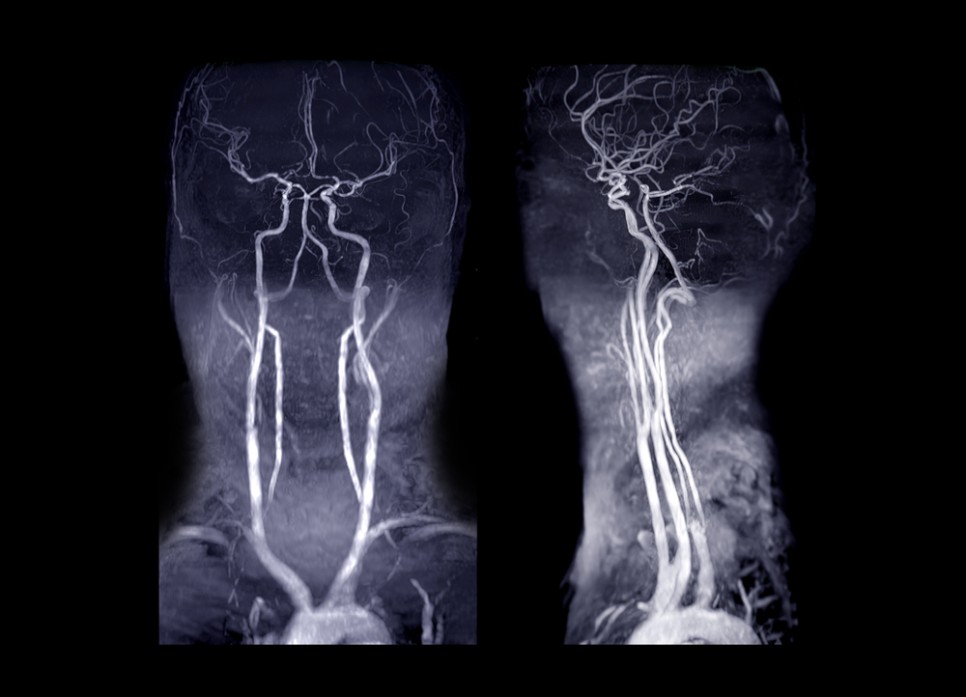

경동맥협착증은 여러 진단검사를 실시한 후 심하지 않을 경우 약물치료를 합니다. 경동맥협착증 진단검사는 경동맥초음파검사, 컴퓨터단층촬영(CT), 자기공명영상(MRI), 경동맥혈관조영술 등을 시행합니다. 혈관조영술은 요즘은 잘 사용하지 않아요.

경동맥 초음파 검사(동맥 경화 검사)는 목 부위에 있는 동맥을 초음파로 확인하는 검사입니다. 이 경동맥초음파검사를 통해 경동맥경화검사 및 편두통의 원인확인, 뇌혈액순환상태를 확인할 수 있습니다.